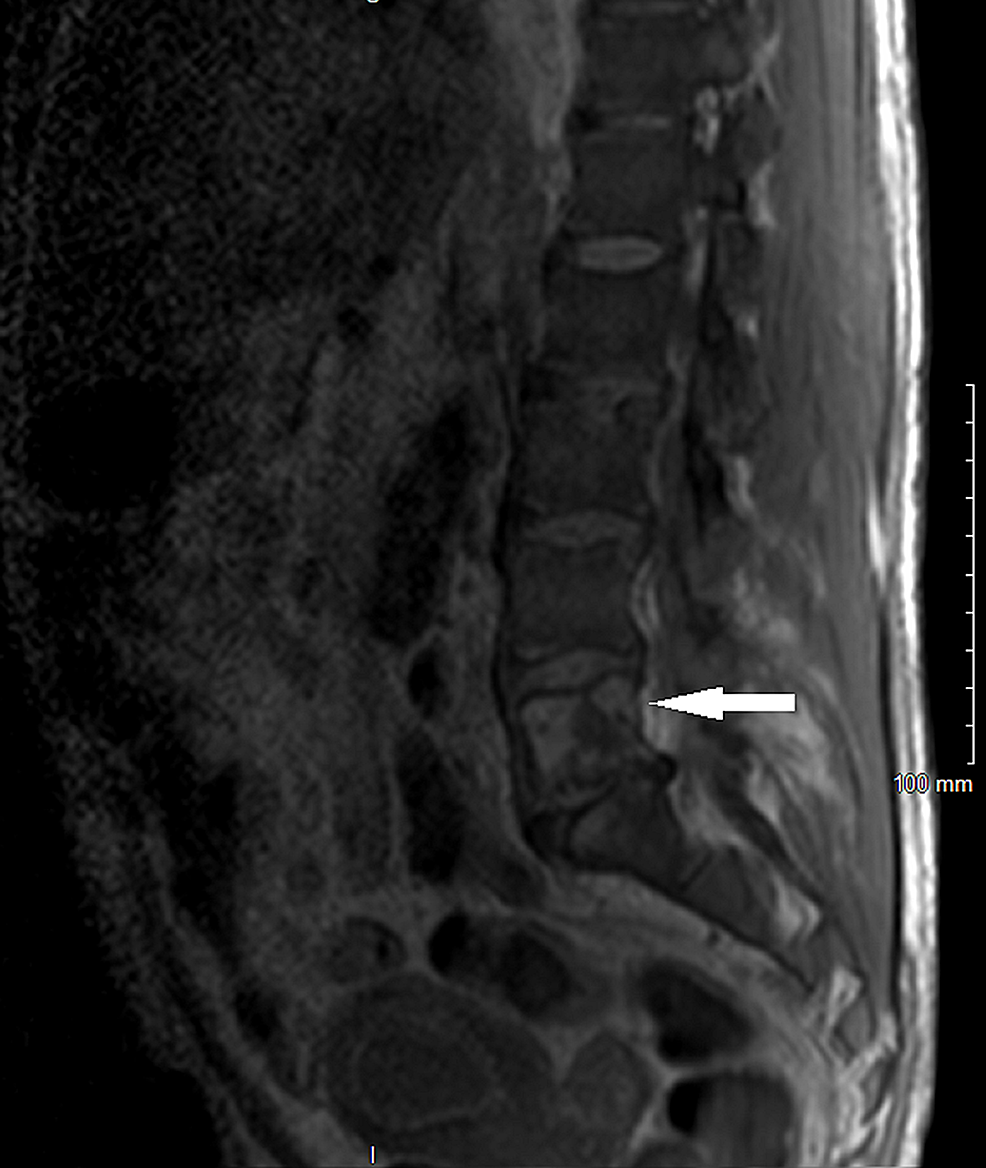

From www.alamy.com

Spine metastasis ( cancer spread to thoracic spine ) ( MRI of thoracic Spinal Cancer Lesions What are the types of spine tumors? Most vertebral tumors are caused by. Learn about 16 types of benign and malignant spinal tumors as well as what symptoms to watch out for and how they can be diagnosed. Spinal cancer involves abnormal cell growth found in the tissues that make up the spine (including the spinal canal and the vertebrae),. Spinal Cancer Lesions.